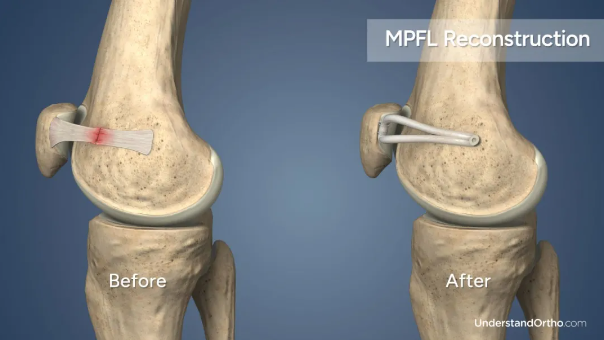

MPFL二联手术过程

(1)切口与暴露

在膝关节前内侧做小切口,分离皮下组织,暴露股骨内侧髁和髌骨内侧缘。

(2)韧带重建

取自体肌腱(如半腱肌)或人工韧带,在股骨侧钻孔固定,另一端缝合至髌骨内侧缘,重建MPFL。

(3)关节镜辅助

通过关节镜清理关节内增生组织,检查髌骨轨迹,确认重建韧带张力是否合适。 (4)闭合切口

逐层缝合切口,加压包扎。